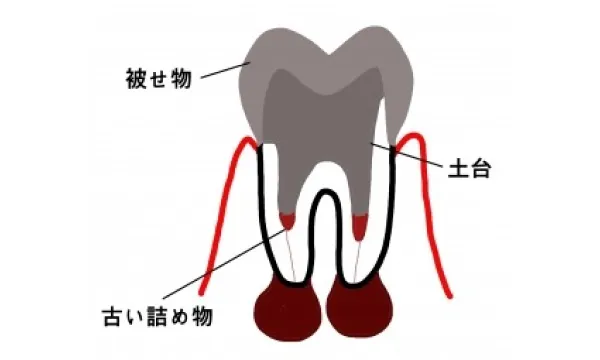

根の治療のやり直しの場合

根の治療のうち過去に根の治療をして神経はないが痛みがある、あるいは化膿して膿が出ていたり腫れている場合の治療手順をご説明します。 根の治療のやり直しの問題点は、本来の神経入っていたトンネルが、ふさがっていたり道がそれていることがあることです。当然、神経をとる根の治療より難易度が上がります。また、非常に炎症が強い場合はすぐに根の治療を始められないことがあります。この場合は、一時的に薬を飲んでもらったり、切開して膿を出したりして炎症を弱める治療をまずする必要があります。 やり直し治療の手順は、まずついているかぶせものや土台をとります。当然とれないようについているのでとるには時間がかかり、歯質は極力削れないようにするので顕微鏡を使って慎重に削っていきます。

すると、根の中の詰め物が見えてきます。この古い根中の詰め物(多くはゴムや練り薬、まれに根の治療器具など)を取り、腐敗した残存物を取り除きます。トンネルの開通や修正を行い、根の先まで長さを慎重に測り、清掃する長さを決定し、その位置まで清掃、拡大を行います。 清掃は、器具によって機械的にトンネルを拡大するのと薬物によって化学的に拡大します。薬を使って安静と再感染を防ぎ炎症が消退したら根の中に滅菌されたゴムを圧力をかけてつめ根の治療を終わります。